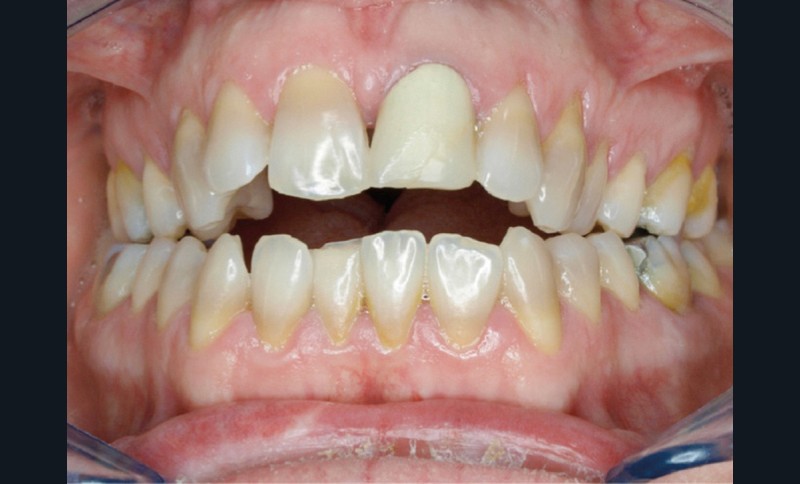

En 2008, la patiente, âgée de 34 ans, se présente pour le traitement de ses « dents mal placées, et de l’écart entre les dents du haut et du bas » (fig. 1). Elle a déjà bénéficié d’un traitement adolescent par plaque amovible maxillaire.

Au niveau exobuccal, la patiente présente un visage convexe avec un étage inférieur de la face augmenté et une absence de contact bilabial au repos traduisant un contexte dysfonctionnel. Le sourire est gingival et étroit.

L’analyse endobuccale et l’étude céphalométrique (fig. 2, tableau 1) confirment le diagnostic de classe II squelettique hyperdivergente avec une classe II molaire et canine bilatérale, associée à un encombrement, à une dysharmonie du sens transversal par endoalvéolie maxillaire, et une béance antérieure par infra-alvéolie incisive maxillaire dans un contexte dysfonctionnel de la musculature péri-labiale et mentonnière.